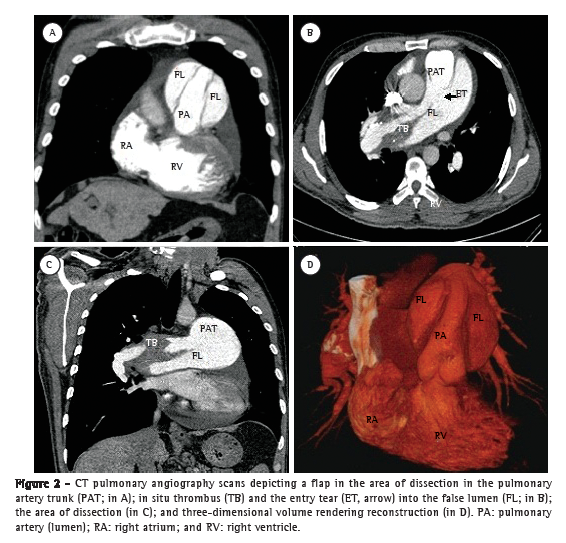

Case reportA 50-year-old male patient diagnosed four years prior with pulmonary hypertension related to schistosomiasis mansoni was admitted to the emergency room of the Federal University of Minas Gerais School of Medicine Hospital das Clínicas, located in the city of Belo Horizonte, Brazil. He presented with new onset, progressively worsening retrosternal chest pain and shortness of breath (functional class III pulmonary hypertension according to the World Health Organization). He had been diagnosed with chronic myeloid leukemia seven months prior and had since been on chemotherapy. At admission, transthoracic echocardiography revealed a large non-obstructive central thrombus in the right main pulmonary artery. The right atrium was dilated, and there was mild tricuspid regurgitation, with an estimated pulmonary artery systolic pressure of 63 mmHg. He was diagnosed as having in situ thrombosis as a complication of the long-standing pulmonary hypertension. After the possibility of acute coronary syndrome had been excluded, he was discharged on warfarin. He was re-admitted two months later due to progressively worsening, refractory chest pain. At that time, he had an SpO2 of 96%, and a third heart sound was audible at the lower left parasternal space, accompanied by a murmur of tricuspid regurgitation. The lungs were clear, and the peripheral arterial pulses were symmetric. Laboratory test results were unremarkable, including serum levels of creatine kinase, creatine kinase MB isoenzyme, and troponin. A resting electrocardiogram showed evidence of acute myocardial ischemia in the anterior leads. Transthoracic Doppler echocardiogram revealed a pulmonary artery systolic pressure of 62 mmHg, a thrombus in the right pulmonary artery, as in the previous examination, and the presence of a flap at that level that was compatible with pulmonary artery dissection (Figure 1). The diagnosis was confirmed by subsequent CT pulmonary angiography (CTPA; Figure 2). He was transferred to another cardiovascular treatment facility, where attempts were made to correct the defect with an endovascular procedure (via the femoral vein). During the perioperative period, the patient presented with refractory cardiogenic shock. Multiple efforts to resuscitate the patient were unsuccessful, and he died in the operating room.

To our knowledge, this is only the second report of a case of pulmonary artery dissection in a patient with schistosomiasis-related pulmonary hypertension, the first such case having been diagnosed at autopsy.(6) Clinically, these cases present with aggravation of previous symptoms of dyspnea and chest pain. The chest pain is typically sharp and can mimic acute coronary syndrome or acute aorta dissection. Cyanosis can be present.(7) The diagnosis is often obtained postmortem, because most patients die suddenly due to cardiac tamponade or severe pulmonary bleeding. If the diagnosis is made antemortem, the first finding is the emergence of a flap in the lumen of the dilated pulmonary artery or trunk formed from the intimal layer, denoting the entry tear into the false lumen but rarely an exit, which is the opposite of what is found in cases of aortic dissection.(8) Magnetic resonance imaging or CTPA of the chest can confirm the diagnosis and the associated complications, such as an increase in pulmonary artery dilatation, bloody pleural fluid, and pulmonary opacities.(1) The evolution is usually rupture of the vessel with blood flowing into the mediastinum, pericardium, or lung, because there is no exit from the false lumen. The intimal tear that leads to the dissection occurs at the point of greatest dilatation as a consequence of an increased parietal tension. It has been reported that inflammation due to in situ thrombosis can play a synergistic role in the development of the intimal disruption.(4,9,10)